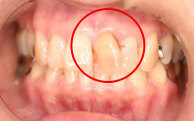

女性Mさん 70代(オールセラミック冠)

主訴

右前歯が動く。

治療内容

水平に破折していました。破折していた部分を取り除き、根管治療をし、ファイバーコアをいれ、オールセラミック冠を被せました。

所感

今まで、他の歯を治療した時は、すべてメタルフリーの治療をされていて、オールセラミック冠の良さを実感されていましたので、今回もオールセラミックを選択されました。

オールセラミック冠(失活歯):¥104,500(税込)

Before

破折した部分を取り除いたところ

After

根管治療後